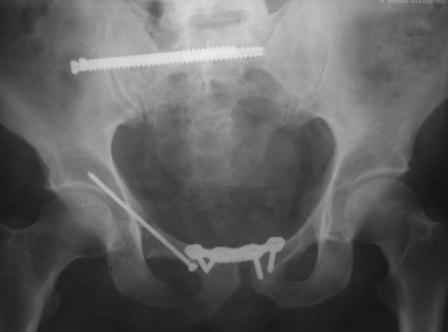

в архиве нашел подобный случай

С Уважением А.Миронов(Новокузнецк)